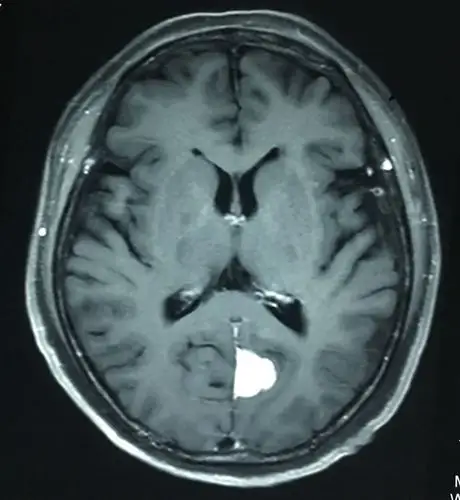

侧脑室内脑膜瘤的手术策略

脑膜瘤是成年人常a见的良性肿瘤,应早期发现,在保护脑神经功能的前提